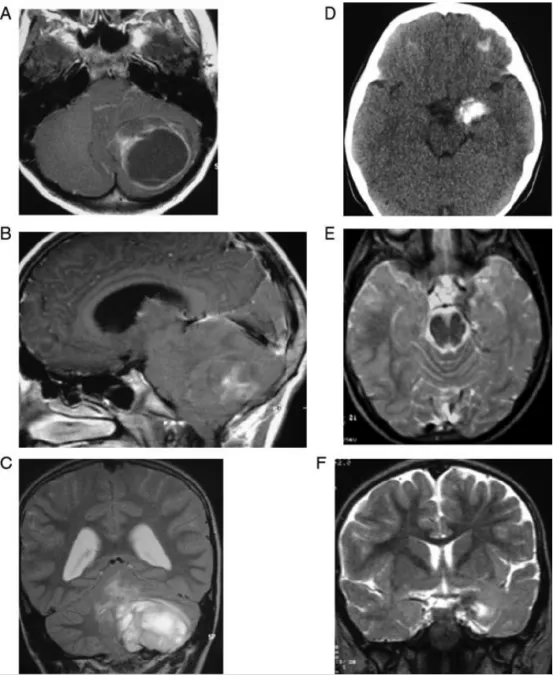

病例一:肿瘤体积/占位效应与神经认知状态缺乏对应关系(A-C)

左侧小脑半球巨大毛细胞型星形细胞瘤(WHO I级)术前MRI表现:

(A)轴位增强T1WI:显示巨大囊性肿瘤,囊壁强化,明显推压小脑及脑干

(B)矢状位增强T1WI:继发枕骨大孔扁桃体下疝(幕下高压所致)

(C)冠状位T2WI:伴有脑积水

尽管存在显著占位效应、扁桃体下疝及脑积水,该患儿认知功能正常。

病例二:肿瘤体积/占位效应与神经认知状态缺乏对应关系(D-F)

左侧颞极内侧小神经节细胞胶质瘤术前CT/MRI表现:

(D)平扫CT:病灶广泛钙化,无水肿

(E)轴位T2WI:肿瘤局限于颞叶钩回

(F)冠状位T2WI:占位效应轻微

尽管病灶小、局灶效应极轻,患儿却表现为重度精神发育迟滞及孤独症样行为。